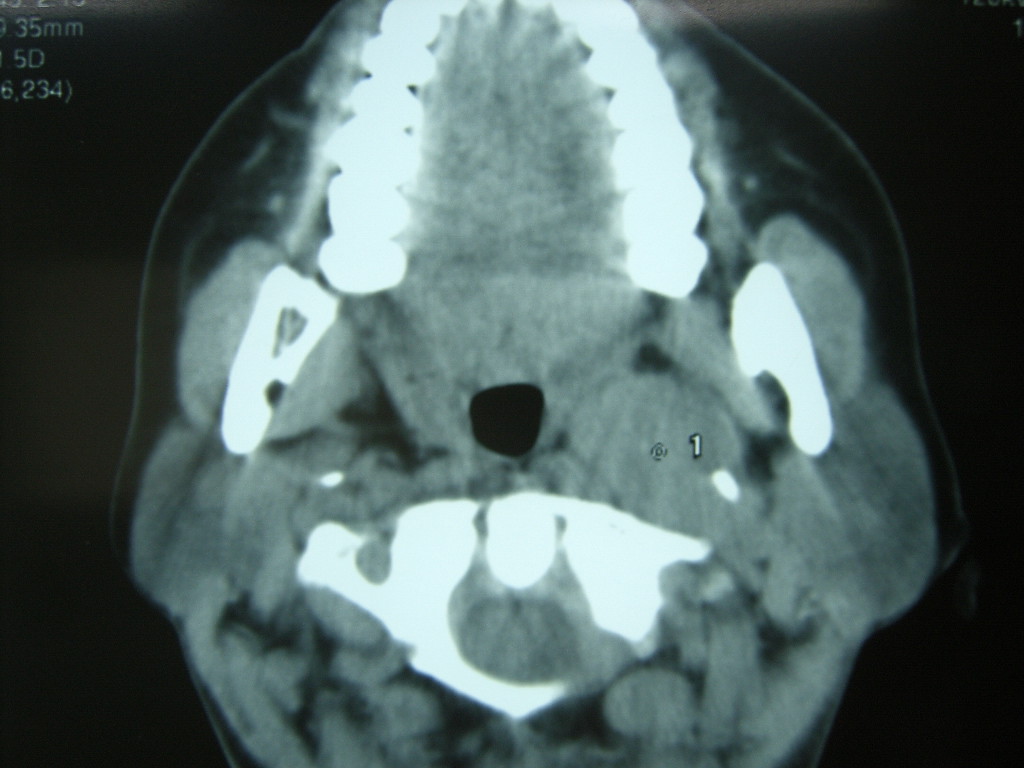

女,48岁,左颈部增粗,不适一年,伴左侧面麻.

增强明显,考虑左侧颈动脉体瘤可能性大。

答案:颈动脉体瘤  此患者已于赤峰220医院手术,